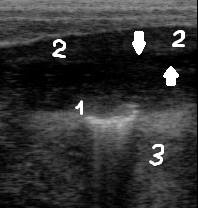

При остром послеродовом метрите клинически

наблюдались повышенная температура тела, кровянистая густая масса; при

ректальной пальпации матка обнаруживалась в брюшной полости, была болезненна и

уплотнена. При этом на ультрасонограмме визуализируется значительное утолщение

сосудистого и мышечного слоёв, последний утолщён и выглядит гиперэхогенным, что

придает стенке матки слоистый вид. Характерным является отсутствие

визуализируемых карункулов и наличие в полости матки гипоэхогенной жидкости с

гиперэхогенными включениями («метель») (рис. 3).

Рис. 3. Ультразвуковая картина

при послеродовом метрите.